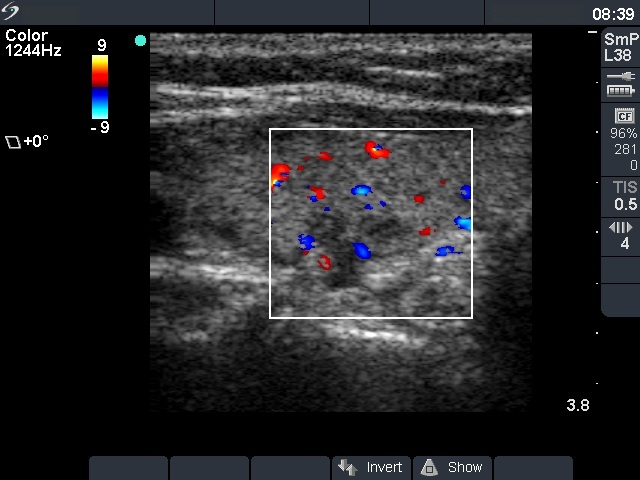

Three years after surgery (fourth row of images)

Ultrasonography: The pattern remained unchanged.

Six years after surgery (third row of images)

Ultrasonography: unchanged.